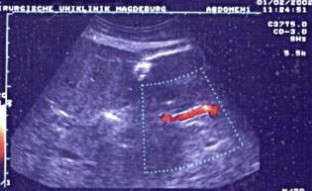

Wir berichten über das diagnostische und therapeutische Vorgehen anhand von 7 Patienten mit Blutungen aus der A. gastroduodenalis (n=5) nach pankreaschirurgischen Interventionen bei Pankreaskopfkarzinom, Rezidiv eines Liposarkoms und chronischer Pankreatitis, der A. hepatica communis (n=1) bei chronischer Pankreatitis und der A. mesenterica superior (n=1) nach akuter Pankreatitis. Anhand von 4 Kasuistiken werden unsere Erfahrungen mit der Implantation von Stentgrafts (Hemobahn®-Prothesen) vermittelt. Den Vorteil der Stentgrafts sehen wir in der sofortigen Blutstillung bei fehlendem Kontakt der Endoprothese zu infiziertem Gewebe und Erhalt der Perfusion des abhängigen Organs. Unsere positiven Erfahrungen mit diesen interventionellen Therapieverfahren erfordern jedoch weitere klinische Untersuchungen, wobei im Mittelpunkt die Indikationen, die technische Erfolgsrate, die stentbedingten Komplikationen und die Langzeitverläufe stehen sollten.

Spontaneous or postoperative hemorrhage into the abdominal cavity due to inflammatory vessel arrosion represents an uncommon but menacing situation. According to the literature, such hemorrhage is associated with a lethality of nearly 2%. Therapeutical options include reoperation and interventional radiological techniques such as endovascular catheter techniques with stent graft implantation or the embolization of vessels. We report on the management of seven cases with hemorrhage either from the gastroduodenal artery (n=5) following pancreatic surgery for pancreatic carcinoma, liposarcoma, and chronic pancreatitis or from the common hepatic artery (n=1) and the superior mesenteric artery (n=1) following chronic pancreatitis. The present article describes our experiences with stent graft implantation (hemobahn prosthesis) in four cases. Based on these experiences, we see the advantages of stent grafts in primary hemostasis without any contact to infected tissue and the preservation of regular perfusion. However, further clinical data are required focussing on indication, technical success rates, stent-related complications, and long-term outcome.